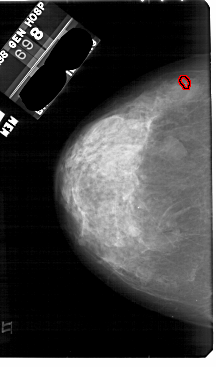

A_1844_1.RIGHT_CC

RIGHT_CC LINES 5251 PIXELS_PER_LINE 2971 BITS_PER_PIXEL 12 RESOLUTION 43.5 NON_OVERLAY

FILE: A_1844_1.LEFT_CC.OVERLAY

TOTAL_ABNORMALITIES 1

ABNORMALITY 1

LESION_TYPE CALCIFICATION TYPE PLEOMORPHIC DISTRIBUTION CLUSTERED

ASSESSMENT 4

SUBTLETY 3

PATHOLOGY BENIGN

TOTAL_OUTLINES 1

BOUNDARY